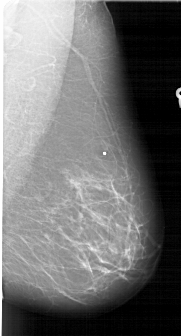

A_1687_1.LEFT_CC

LEFT_CC LINES 6466 PIXELS_PER_LINE 3706 BITS_PER_PIXEL 12 RESOLUTION 43.5 OVERLAY

FILE: A_1687_1.LEFT_CC.OVERLAY

TOTAL_ABNORMALITIES 1

ABNORMALITY 1

LESION_TYPE MASS SHAPE LOBULATED MARGINS ILL_DEFINED

ASSESSMENT 4

SUBTLETY 4

PATHOLOGY BENIGN

TOTAL_OUTLINES 1